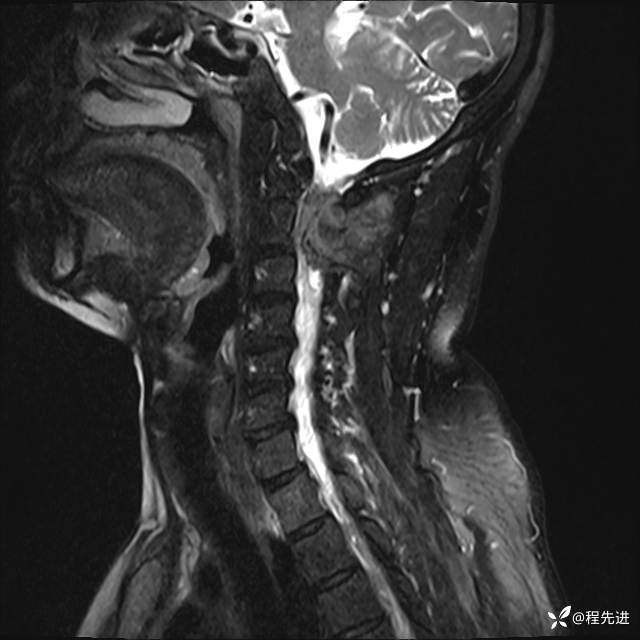

MRI平扫+增强:

T1: